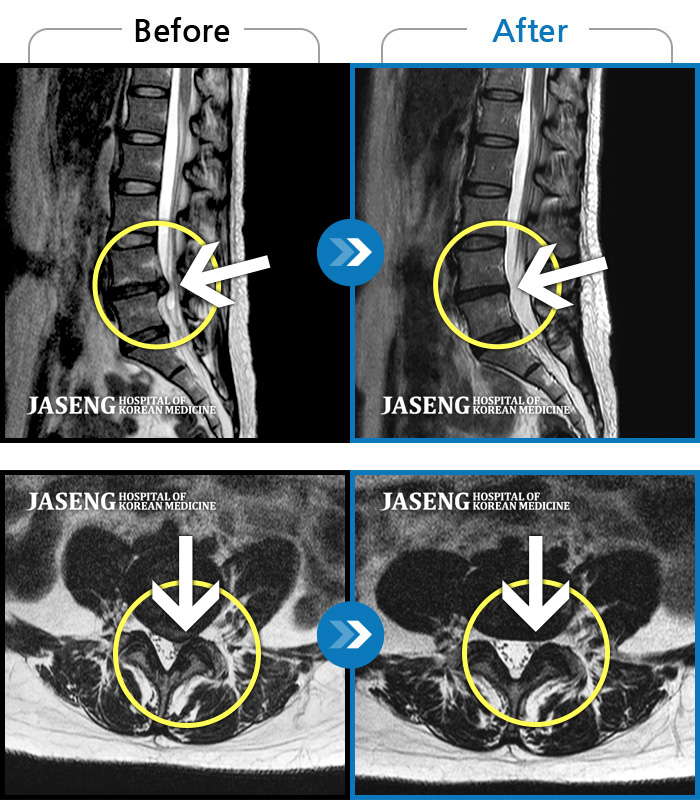

ȯںп Ǹ ǿ ԿǾ, ο ġ ۿ Ƿ ġḦ Ͻñ ٶϴ.